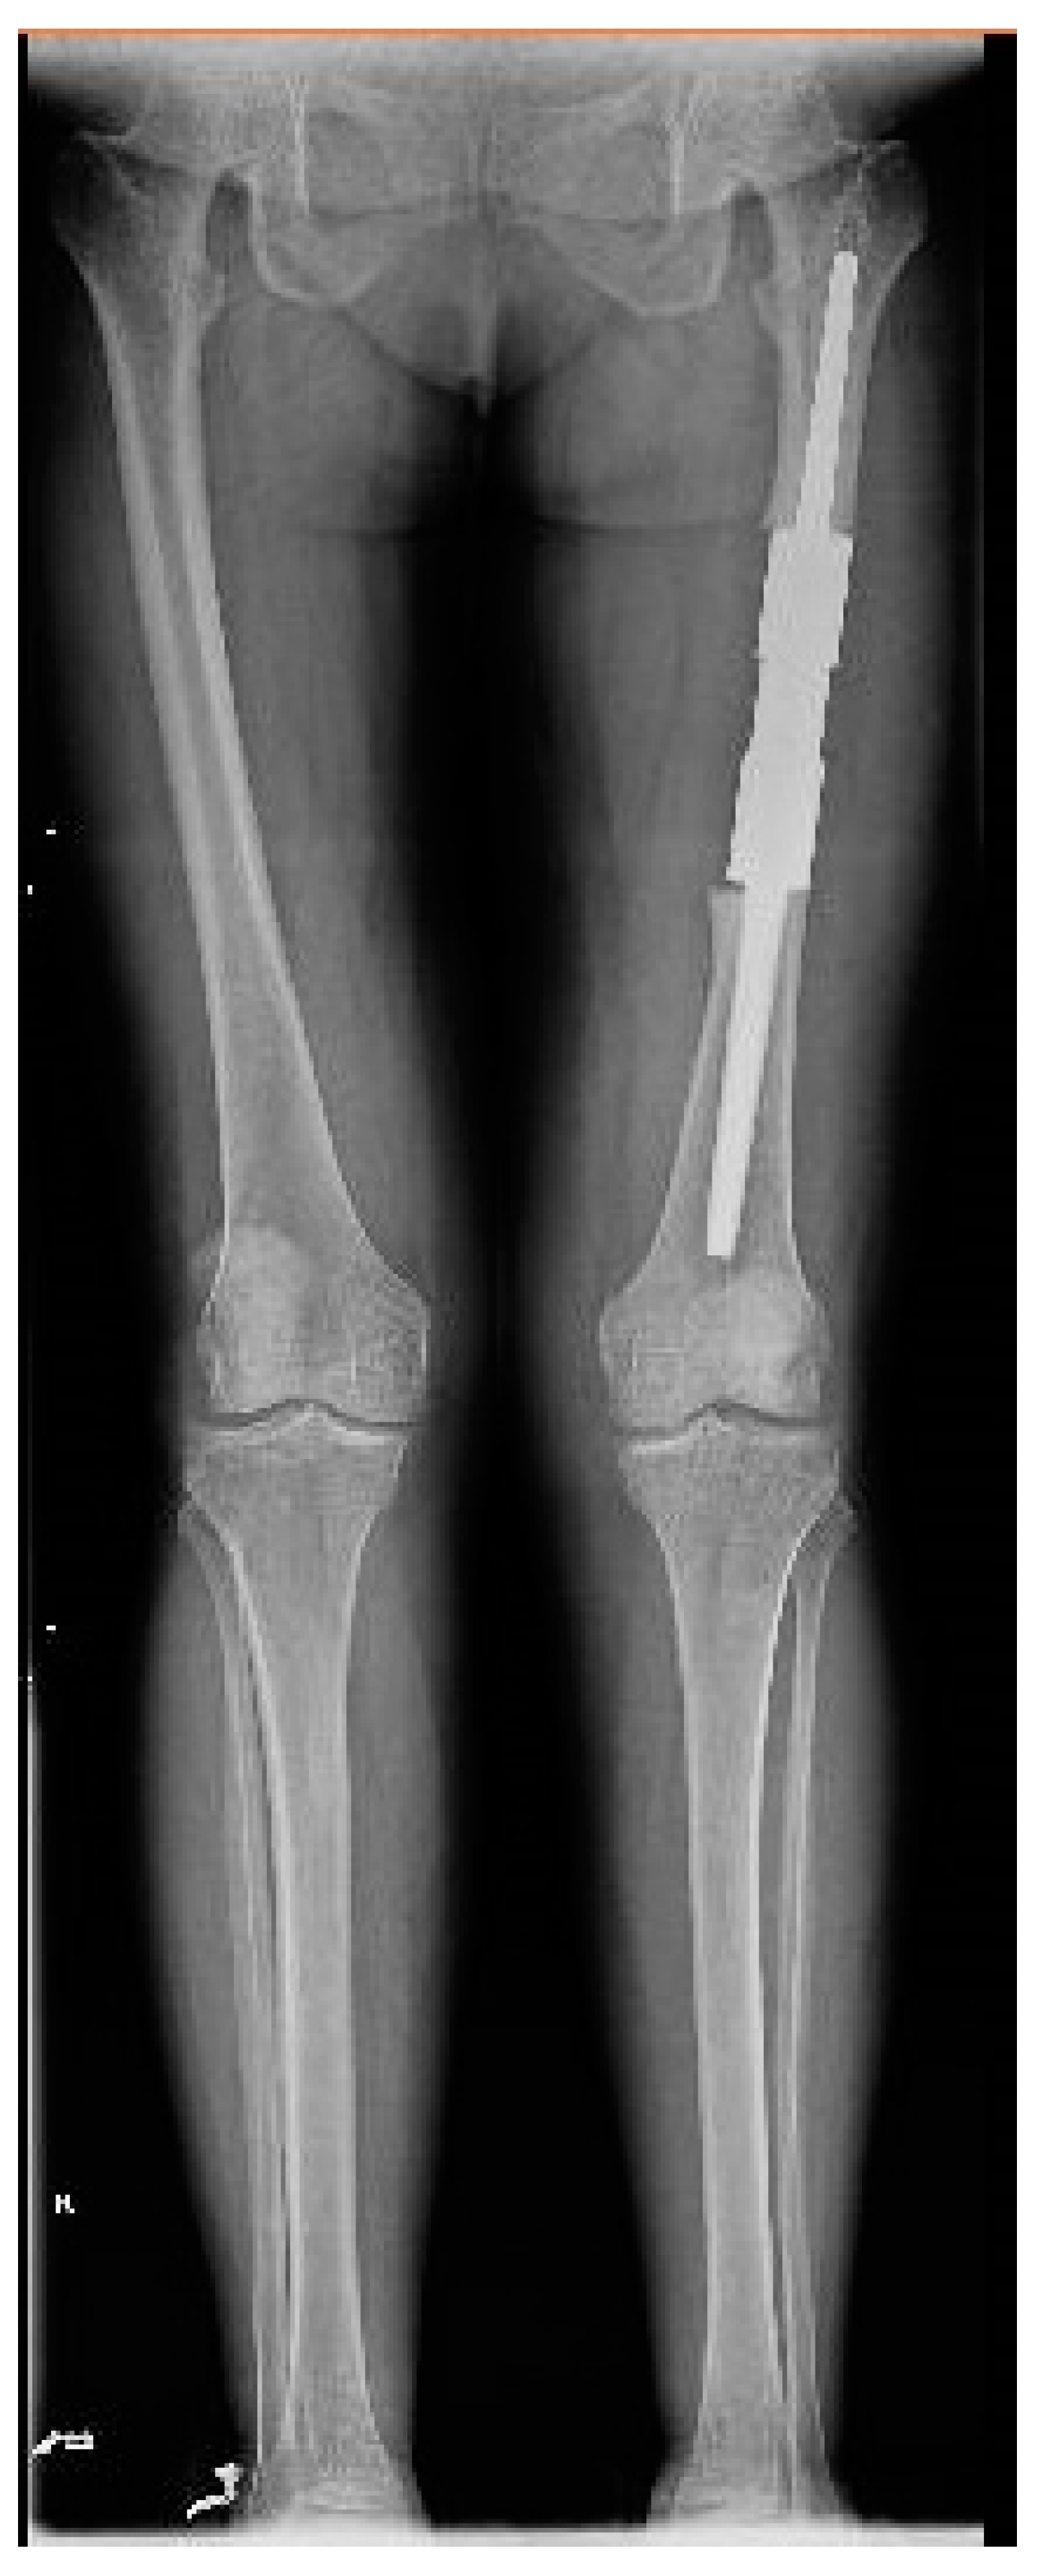

The patient was discharged with the recommendations of analgesic and anti-inflammatory treatment in high doses, and she was included in a medical recovery program. The patient was included in the full medical recovery program for eight weeks in a specialized medical center, during which she also received anti-analgesic treatment in maximum doses, but without improvement regarding symptoms. Taking into account the chronic evolution of the pain, the complete lack of response to conservative treatment after eight weeks, and the lack of treatment guidelines in the case of melorheostosis, a surgical approach needed to be considered. Thus, the patient returned to the orthopedic department with significant pain, gait deformation, and a decreased ability to flex the thigh and extend the knee. Considering the size of the lesion, its location, with the increased potential to cause compression of the vessels and the femoral nerve, the lack of changes in the soft tissues, and the symptoms not being responsive to conservative treatment, as well as a histopathological result of a benign lesion, choosing the best treatment was a challenge for the surgical team. Although it was a benign lesion, the important impact on the quality of life together with the failure of non-surgical treatment allowed the consideration of surgical treatment. The patient’s symptoms were mainly determined by the increase in the volume of the tumor and the mass effect on the adjacent tissues, especially on the vessels and the femoral nerve. The surgical option in this case, considering the circumferential location of the lesion at the level of the femoral diaphysis, was a radical one. The surgical approach consisted of segmental resection to healthy bone tissue and reconstruction of the remaining defect with a modular tumoral prosthesis. After adequate preoperative preparation, surgery was performed, and, using a lateral iterative approach, the bone lesion was resected to the normal macroscopic bone tissue (Figure 9). The proximal, distal, medial, lateral, anterior, and posterior resection limits were sent for extemporaneous pathological examination; all of them were negative for tumor invasion. The reconstruction was carried out using a modular diaphyseal segment fixed intramedullary using 10 cm femoral stems (Figure 10). In the preoperative planning, the potential surgical difficulties were related to the correct restoration of the length of the limb, the correct establishment of the rotation of the femur, and obtaining a minimum of 10 cm of healthy bone in the proximal and distal femur after lesion resection so as to allow a good fixation of the implant. The surgery was performed without unique issues, and the postoperative results were optimal with no leg length discrepancy. Taking into account the magnitude of the surgical intervention for this type of benign lesion, the risks, such as deep venous thrombosis, pulmonary thromboembolism, intraoperative vascular-nerve injuries as well as considering the intimate contact of the lesion with vessels and nerves, leg length discrepancy, and the major septic risk, should be remembered. At the 45-day postoperative control, the patient no longer complained of pain in the operated-on limb and was mobile with full support without gait difficulties.

Figure 10. Full-leg X-ray 45 days after surgery.